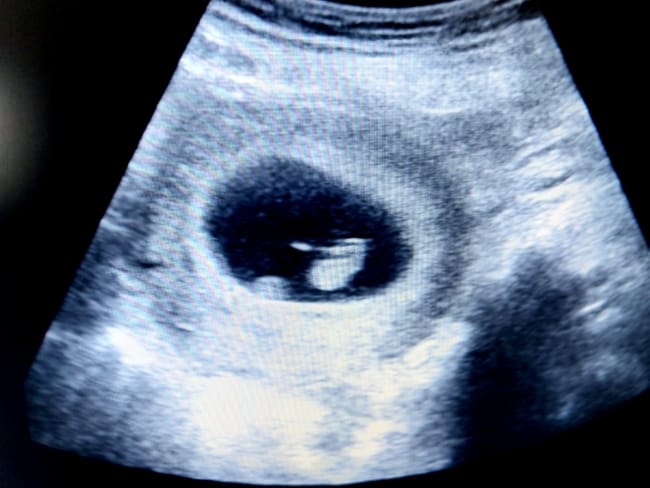

Janin 5 minggu menandakan bahwa kehamilan Bunda sudah memasuki bulan kedua. Di usia ini, ukuran janin memang masih sangat kecil bahkan lebih kecil dari biji wijen, yaitu sekitar 1,5–2 mm. Meski begitu, banyak proses menakjubkan yang sedang berlangsung di dalam rahim Bunda!

Walaupun ukurannya masih sangat kecil, jantung janin 5 minggu sudah mulai berkembang dan mulai berdetak untuk pertama kalinya. Detak jantung ini memang belum bisa didengar melalui USG 2 dimensi, tetapi ini menjadi tanda awal kehidupan yang sesungguhnya di dalam rahim.

Plasenta dan kantung ketuban yang merupakan dua hal penting untuk mendukung kehidupan janin juga mulai terbentuk di usia kehamilan 5 minggu. Plasenta nantinya akan menyalurkan nutrisi dan oksigen dari Bunda ke janin, sekaligus membuang sisa metabolisme janin 5 minggu. Sementara itu, kantung ketuban berfungsi untuk melindungi janin dari benturan dan tekanan dari luar rahim.